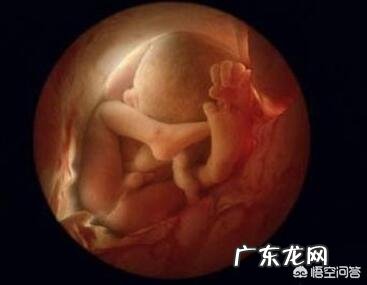

孕33周,胎儿长约41.5cm,重约2000g 。双顶径约8.50±0.47cm,腹围约27.78±2.30cm,股骨长约6.42±0.46cm 。

此时胎儿的头骨特别软,每块骨头中间都有缝隙,主要是为了顺利通过阴道做准备,所以孕妈妈们补钙一定要注意,不要过量哦;此时胎儿的呼吸系统、消化系统、生殖器官几乎发育成熟了,而且胎儿的皮肤变成了粉红色,脂肪也在慢慢堆积,很快就会变成一个胖娃娃了;还有些入盆早的宝宝此时已经入盆了~

孕34周,胎儿长约43cm,重约2300g,双顶径约8.61±0.63cm,腹围约27.99±2.55cm,股骨长约6.62±0.43cm 。

此时胎儿的位置已经开始调整为头朝下的姿势,但是有些胎儿可能胎位不正,横位或者臀围,孕妈妈们需要定期产检,关注胎儿的胎位,如果出现胎位不正得及时调整 。

孕35周,胎儿长约44cm,重约2500g,双顶径约8.70±0.55cm,腹围约27.99±2.55cm,股骨长约6.62±0.43cm 。

胎儿正在努力长大,为分娩做准备,他的头已经转向了下方,头部进入骨盆,而且胎儿的肺部基本发育完全,皮下脂肪也在努力堆积,但是胎儿的中枢神经系统尚未完全发育成熟 。此时孕妈妈需要小心谨慎,避免胎儿早产哦~

孕36周,胎儿长约45cm,重约2700g,双顶径约8.81±0.57cm,腹围约29.44±2.83cm,股骨长约6.95±0.47cm 。

此时,胎儿全身的绒毛和胎脂正在开始脱落,脂肪已经很多了,看起来很漂亮;胎儿的两个肾脏已发育完全,他的肝脏也已能够处理一些代谢废物;很多胎儿此时已经入盆了,妈妈可能出现尿频、耻骨痛的症状,一定要注意休息,好好养胎哦~